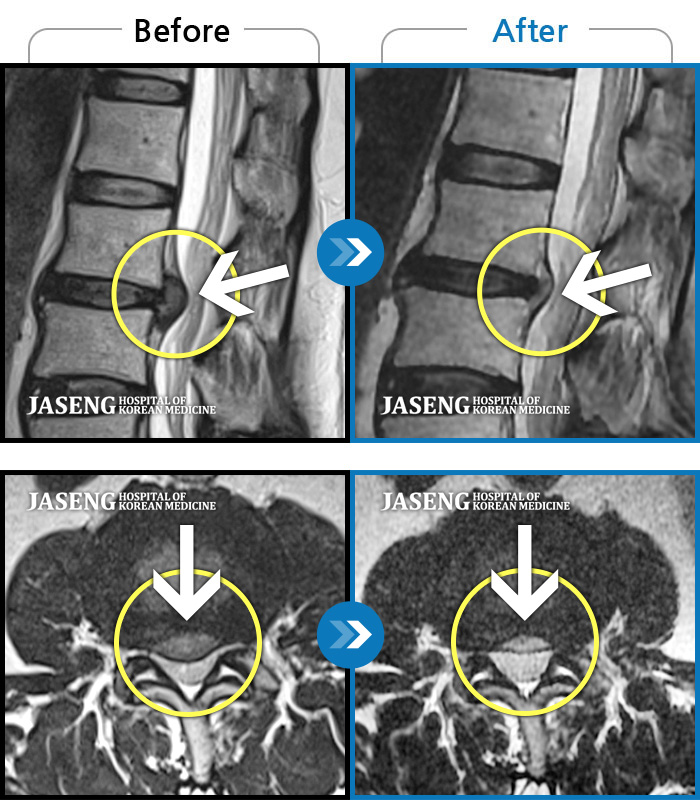

ȯںп Ǹ ǿ ԿǾ, ο ġ ۿ Ƿ ġḦ Ͻñ ٶϴ.